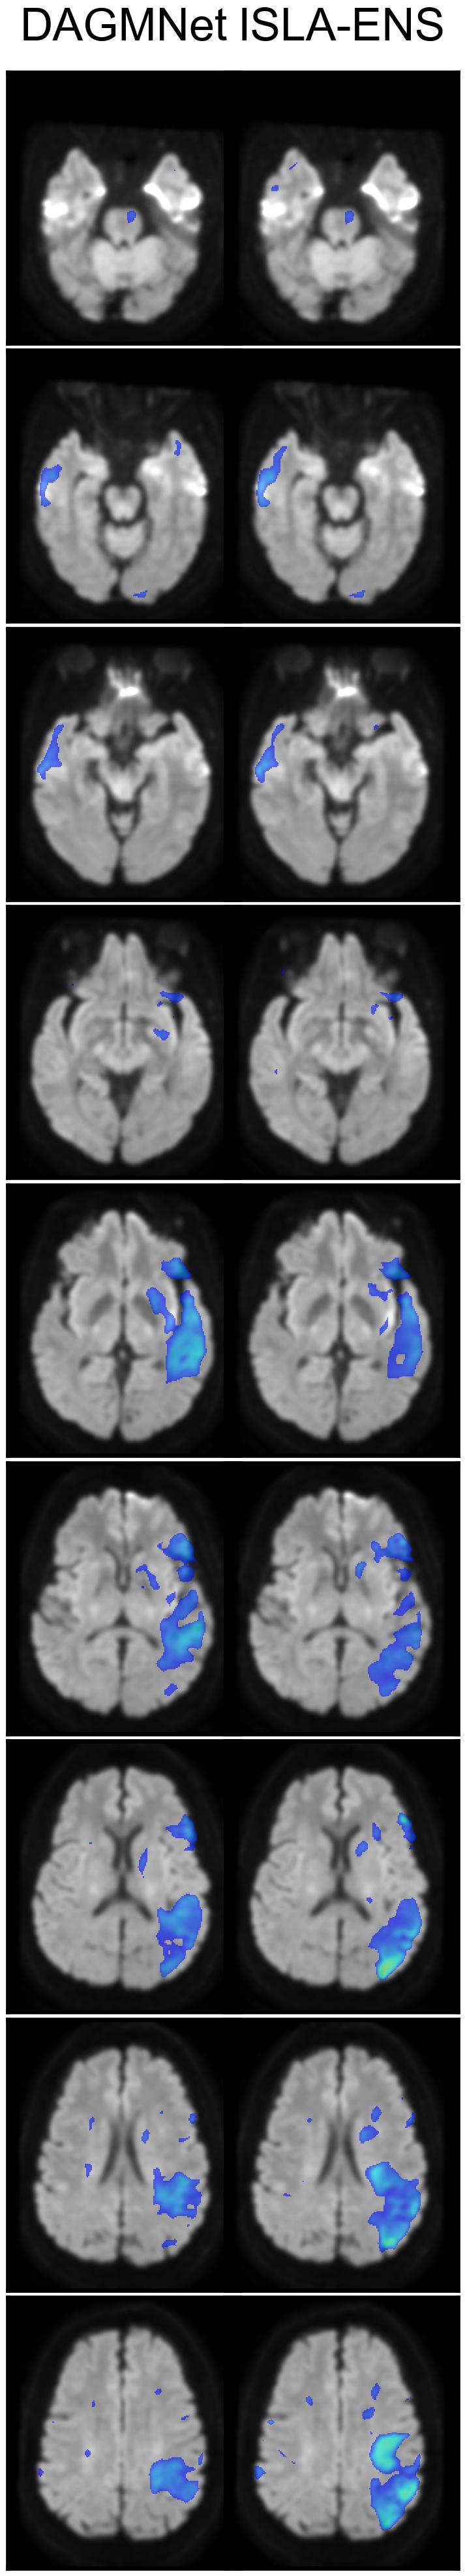

4.2.2.2. Proportions and distances of false positives and false negatives

The FP proportion map (Figure 5(a)) shows that both models exhibited a region of high FP concentration near the right corticospinal tract: slices 5 and 6 for ISLA-ENS, and slices 8 and 9 for DAGMNet. When examining the FN proportion map (Figure 5(b)) alongside it, it can be seen that the region of high FP concentration for ISLA-ENS coincided with lower FN proportions compared with DAGMNet (slices 5 and 6), whereas the converse was not true (slices 8 and 9). This suggests that ISLA-ENS’s tendency to be more sensitive to suspicious areas contributed to improved lesion detection, a pattern not observed for DAGMNet. In addition, ISLA-ENS produced fewer FPs in the superior posterior region of the brain (slices 5–9 in Figure 5(a)) and fewer FNs across a large inferior region (slices 1–7 in Figure 5(b)).

Figure 5(c) further shows that DAGMNet produced FPs that were, on average, farther from any true lesion compared with ISLA-ENS. For example, slices 5-9 exhibit elevated mean HDs in the posterior part of the brain for DAGMNet; most contributing cases displayed inhomogeneity artifacts (D). Slices 1-7 also show high mean HDs in the temporal region (particulary the left) for DAGMNet, likely caused by magnetic-susceptibility artifacts near the ears (D).

To a lesser extent, slices 8 and 9 of Figure 5(c) reveal two regions where both models displayed elevated mean HDs: one at the left posterior boundary and another in a small region along the right boundary. These high distances were attributable to a case with a severe inhomogeneity artifact in the former region and a case with a hematoma in the latter (D).

Regarding FN mean HD, although slightly higher values were observed in the right posterior superior region for ISLA-ENS—corresponding to regions where DAGMNet exhibited substantially higher FP mean HDs (Figure 5(c))—, no region showed comparably large average errors (Figure 5(d)).